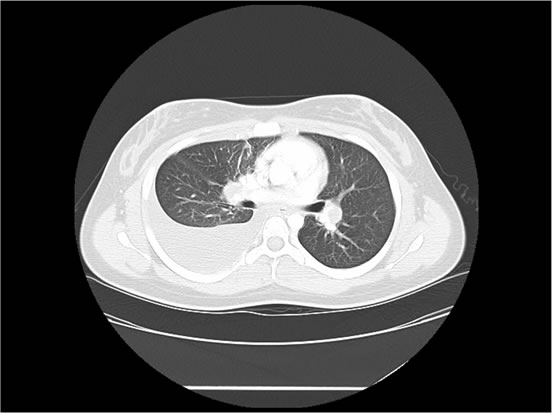

We ordered a CT scan with infusion of the chest

I will show you 12 CT-scan cuts.